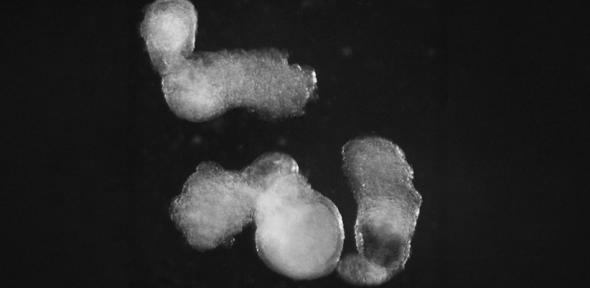

The embryo-like structures, which the scientists have named ‘hematoids’, are self-organising and start producing blood after around two weeks of development in the lab – mimicking the development process in human embryos.

The team observed the emergence of the three-dimensional hematoids under a microscope in the lab. By the second day, these had self-organised into three germ layers – called the ectoderm, mesoderm, and endoderm – the foundations of the human body plan that are crucial for shaping every organ and tissue, including blood.

By day thirteen, the team saw red patches of blood appearing in the hematoids. They also developed a method which demonstrated that blood stem cells in hematoids can differentiate into various blood cell types, including specialised immune cells, such as T-cells.